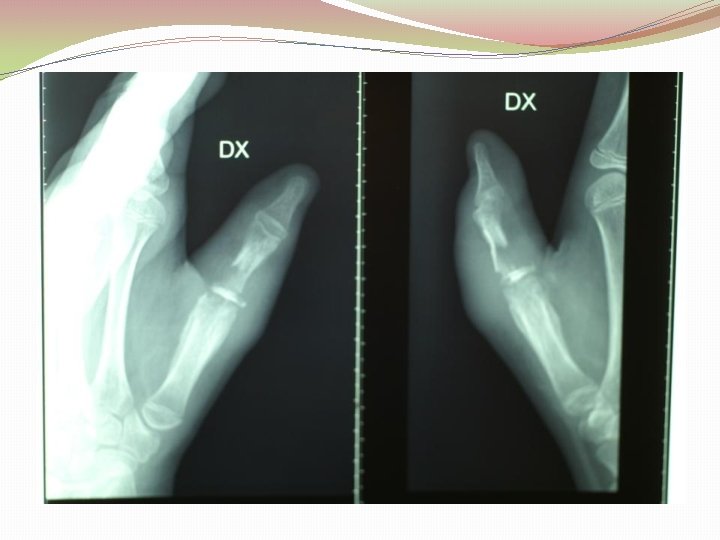

Diagnostika �Klīnika �Laboratoriskie izmeklējumi (asins aina, EGĀ, CRP, uzsējums no brūces) �Kaula palpācija (Probing to bone test) �Rtg, MRI, DT, kaulu scintigrāfija, USS �Kaula biopsija (zelta standarts)

Diagnostika �Rentgena izmeklējumi (x-ray) �Datortomogrāfija �Ultrasonogrāfija �Radionuklīdā skenēšana (Technetium-99 m; Gallium 67 ) �Magnētiskā rezonanse (MRI)